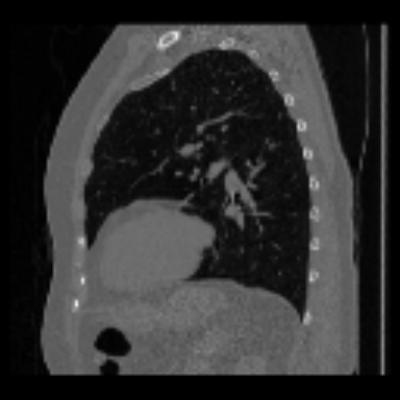

| Axial | Coronal | Sagittal | |

| X2CTGAN | ![]() |

![]() |

|

| DX2CT | ![]() |

| Ground-truth | ![]() |

Figure 3 and Table I(a) using biplanar X-rays show that proposed DX2CT can outperform three existing SOTA methods. Figure 3 shows that DX2CT can provide more accurate overall shapes and details compared to the existing methods. The quality of reconstructed CT slices in the axial plane is less satisfactory than those in the other planes. The reason is that the axial plane is perpendicular to the planes of biplanar X-rays so there exists less spatial (i.e., depth) information in the axial plane. Without using the perceptual loss [33], proposed DX2CT gave comparable LPIPS results with PerX2CTs using [33] in training. Compare their LPIPS results in Table I(a).